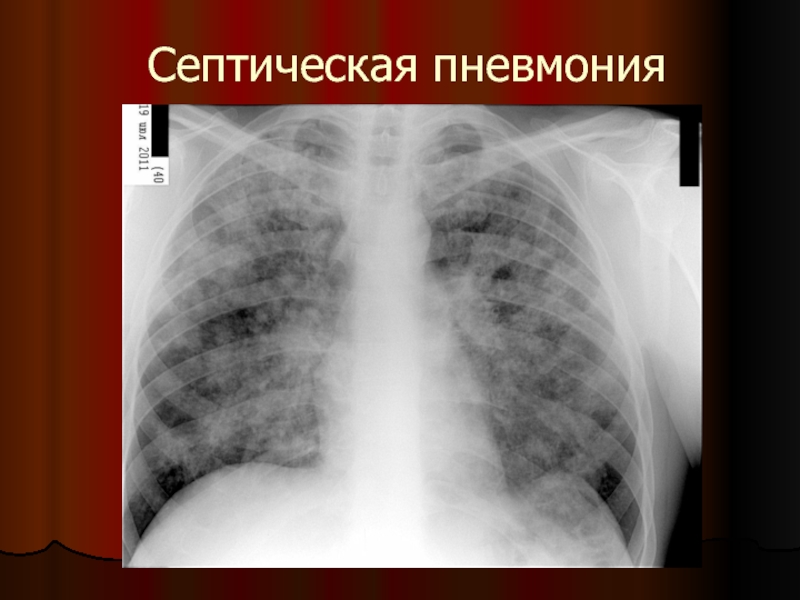

Слайд 12Септическая пневмония

ПЕРВИЧНАЯ (аэрогенная, бронхогенная)

- характеризуется преимущественно односторонними единичными очагами деструкции

ВТОРИЧНАЯ (гематогенная,

лимфогенная)

- Поражение чаще двустороннее в виде множественных мелких очагов